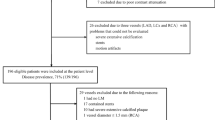

A total of 2,139 reports were identified from PubMed, Cochrane, Embase, and Web of Science. After the removal of 749 duplicate publications, titles and abstracts were checked, and 42 potentially relevant studies were selected. After a thorough full-text review, 18 studies were eligible and included [4, 24,25,26,27,28,29,30,31,32,33,34,35,36,37,38,39]. The literature screening process is shown in Fig. 1.